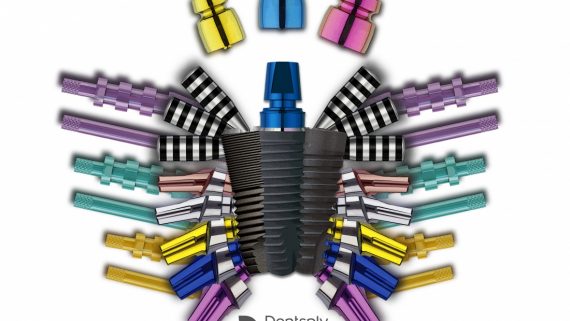

- Инструменты?